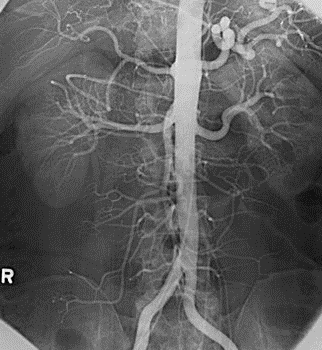

• Aortografía

Aortografía

Conocida gracias a Reynaldo Dos Santos, se sabe que puede realizarse por punción dorsal directa o bajo circulación reducida.